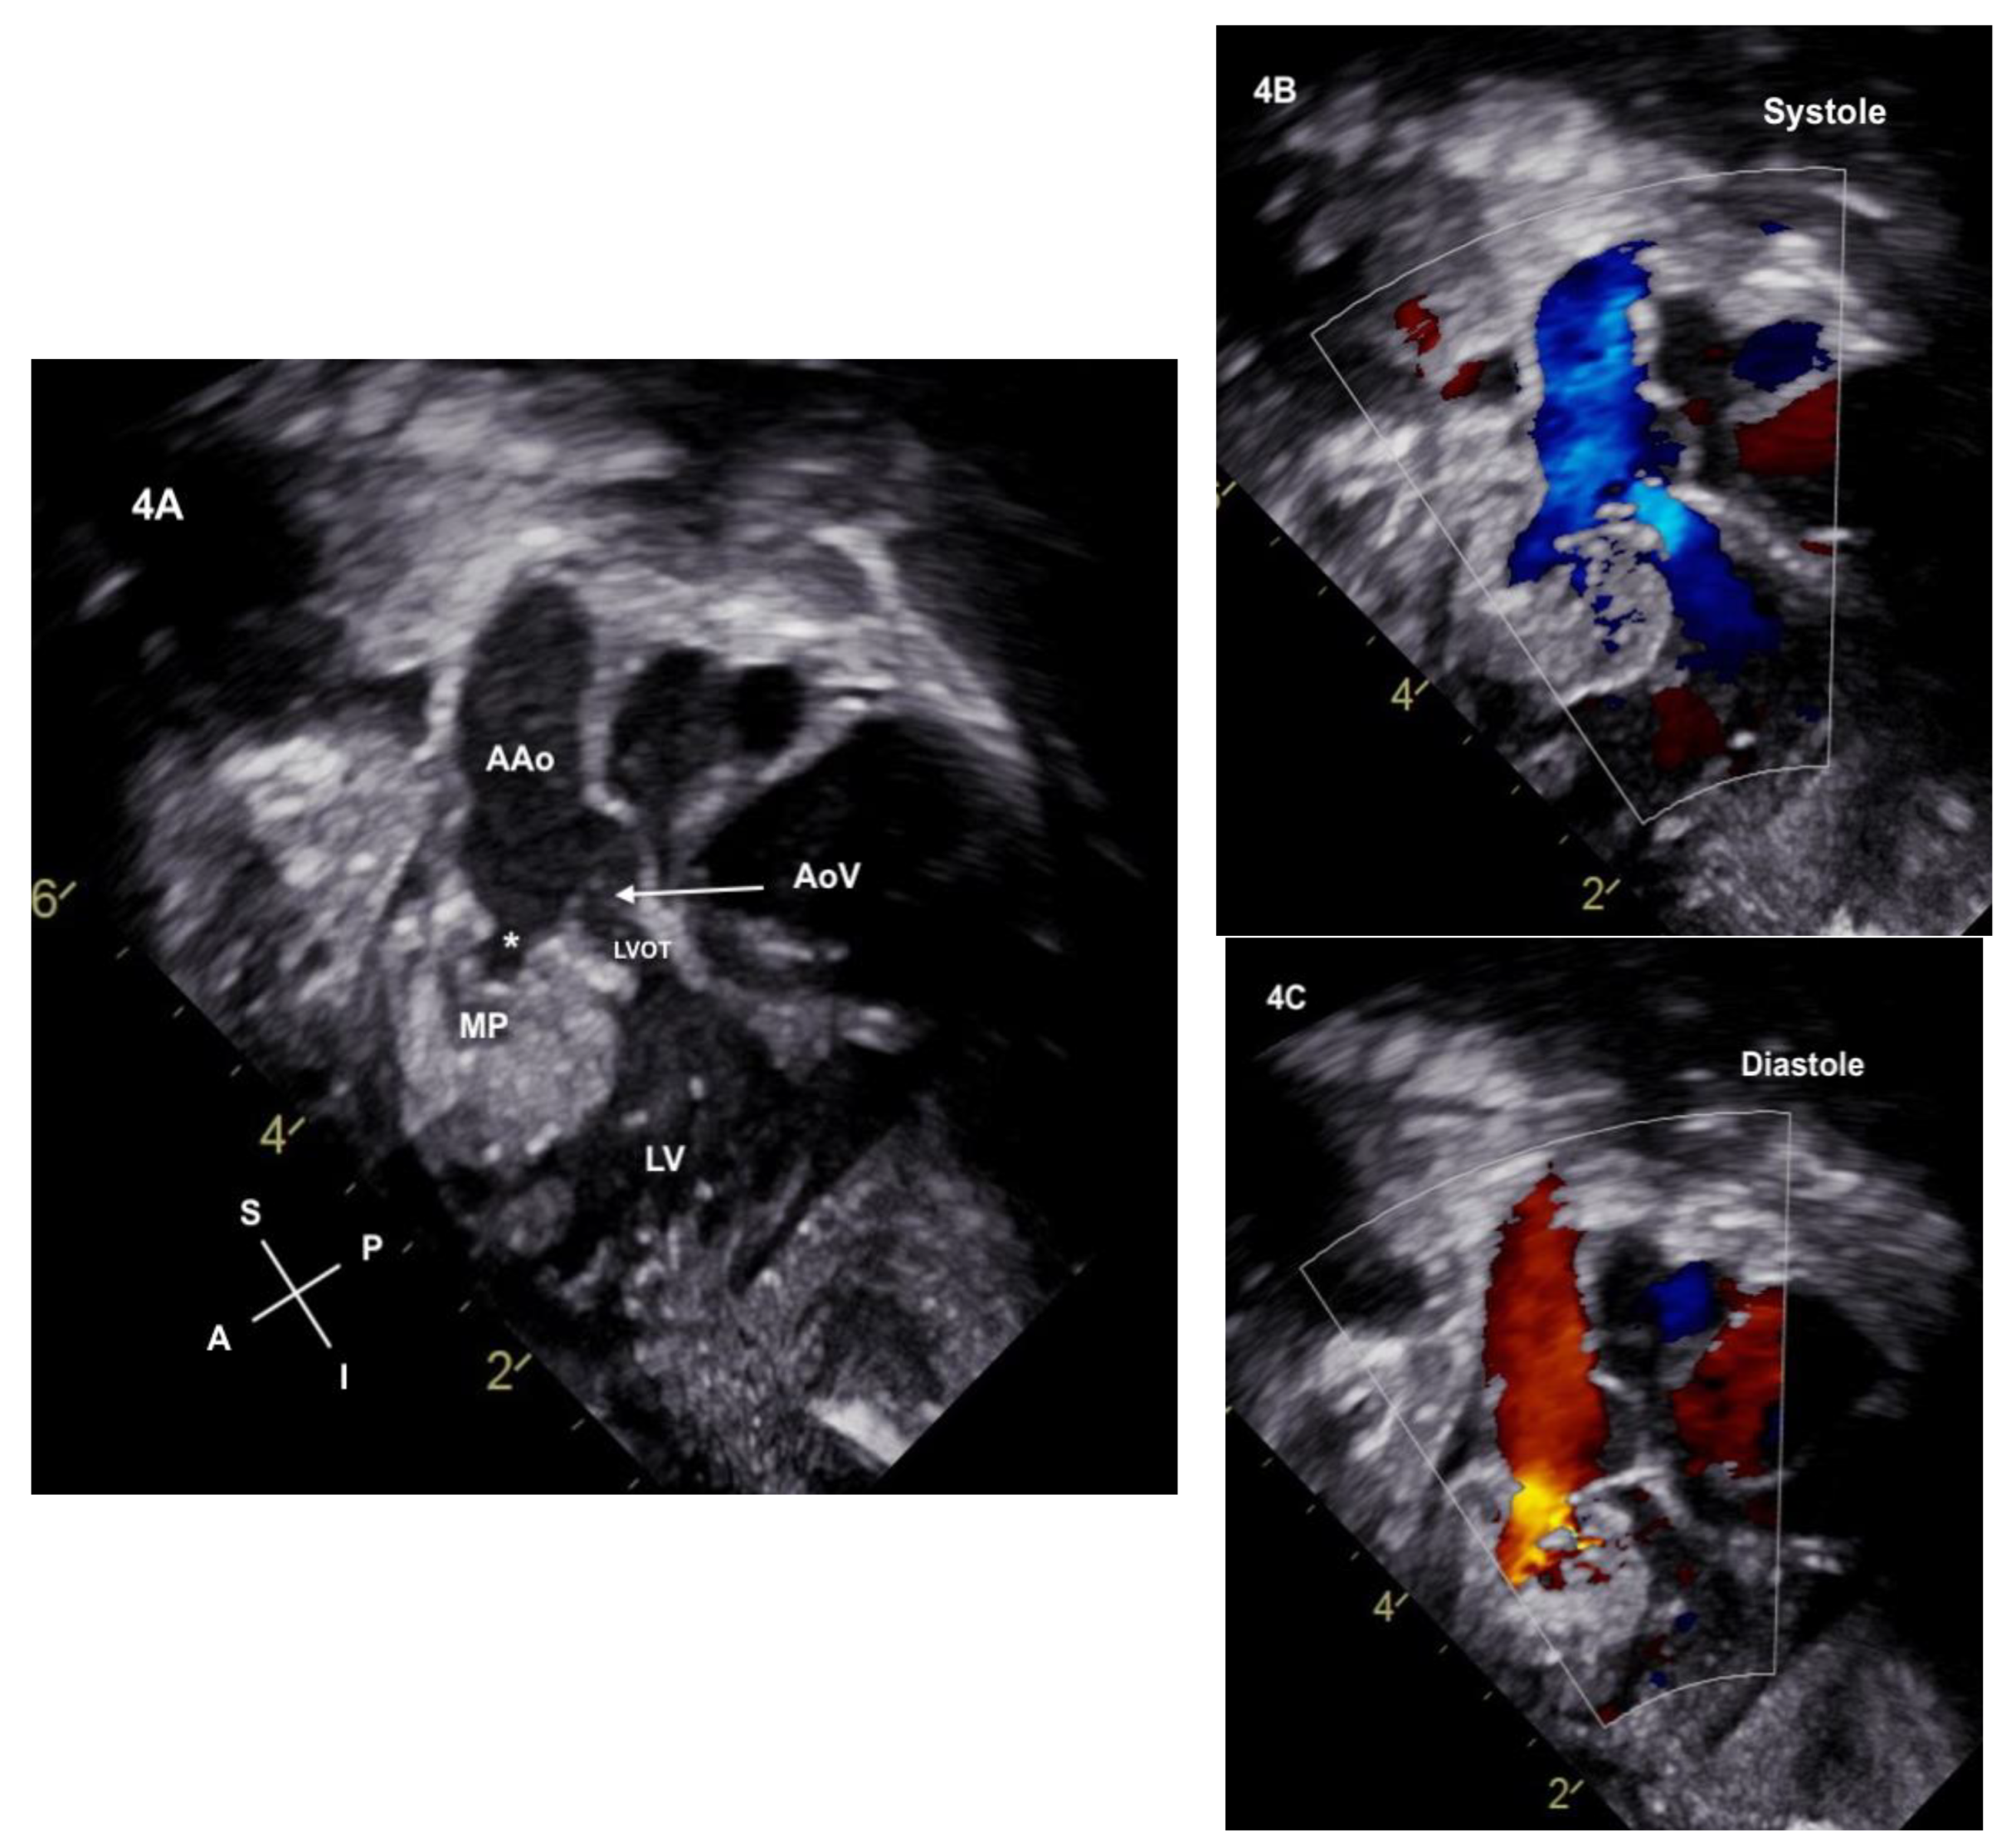

2. Case Description